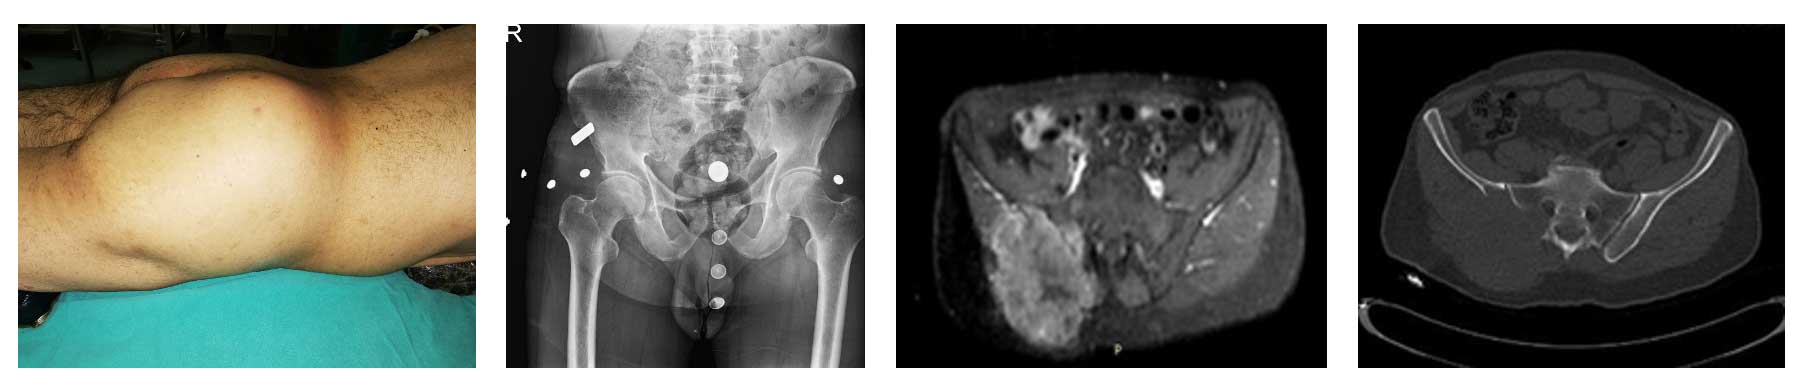

60 yaş erkek hasta. Akciğer kanseri tanısı ile tedavi öyküsü mevcut. Sağ leğen kemiği arka kısmında metastaz nedeniyle daha önce radyoterapi uygulanmış ancak ağrı, şişlik ve yürüyememe şikayetleri tekrarlamıştır.

Ameliyat Öncesi: Klinik olarak şişlik, röntgende ise yeniklik (lizis), MR ve tomografide ağırlıklı olarak leğen kemiğinin arkasında ciddi yıkıma neden olan, sakrumu etkileyen ve büyük bir tümör dokusunun eşlik ettiği metastaz varlığı görülmekte.